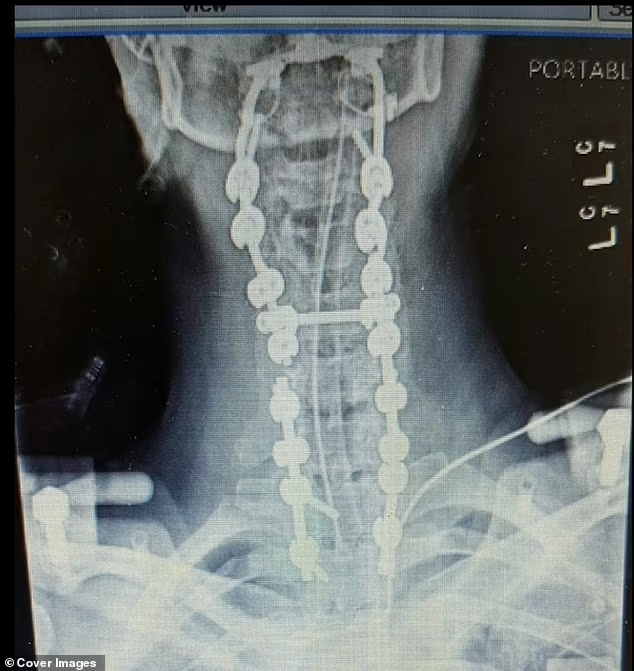

The situation reached a breaking point during a procedure to remove a spinal brace. Megan experienced Atlanto-occipital dislocation (AOD)—a clinical “internal decapitation” where the skull detaches from the spine. With a survival rate of less than 10%, this injury is almost always fatal due to the risk of total paralysis.

Following 37 surgeries, Megan’s spine is now fused from her skull to her pelvis. While she can no longer turn or bend her head, she refuses to let her physical limitations define her.